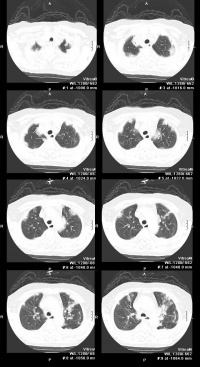

念珠菌性支气管炎,其主要症状为咳嗽及咳出粘液性胶状痰,可从中查出病原菌。本病呈慢性经过,时作时止,对健康影响不大;念珠菌性肺炎,患者常有胸痛,可伴体温增高。多见咳嗽及咯

念珠菌病

出粘稠胶状带有血丝的痰。听诊和X线检查均有异常。病重者,可引起死亡。